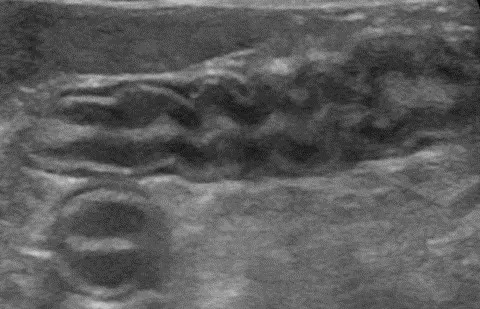

The majority of GI foreign bodies are denser than surrounding soft tissues and fluid. Most of the ultrasonography beam is reflected when there is a sudden change in tissue density (more accurately, acoustic impedance), and further echoes deep to that surface are not produced. The resultant image is a bright hyperechoic line that contours to the shape of the foreign body (eg, plastic toys, rubber balls, cloth, bones, metal), with variable distal acoustic shadowing (Figure 1).9-12 Foreign bodies filled with gas have a similar appearing hyperechoic surface but cause a reverberation artifact (ie, dirty shadow). The entire foreign body will be visible if it is hollow and filled with fluid or has a density similar to soft tissue. Locating foreign bodies can be challenging when only the surface is visualized, but ultrasonography can help detect other changes associated with pyloric outflow, small intestinal mechanical, and linear foreign body obstructions.

Abdominal ultrasound of a 6-year-old neutered male crossbreed dog with a surgically confirmed foreign body (cloth) in the duodenum. The cloth is seen as a hyperechoic curvilinear structure (arrow) that causes a distal acoustic shadow (asterisk).